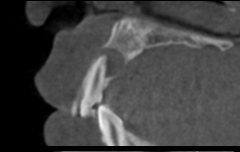

多発性歯根嚢胞を精密根管治療、歯根端切除術を行なった症例

治療前